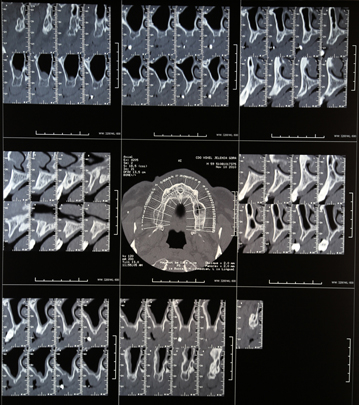

1. Szczegółowa diagnostyka przy użyciu tomografu komputerowego w celu precyzyjnego określenia objętości kości i ustalenia pozycji implantów w żuchwie i szczęce

1. Radiologiczny obraz jamy ustnej z wykorzystaniem tomografu – precyzyjne pozycjonowanie lokalizacji planowanych implantów